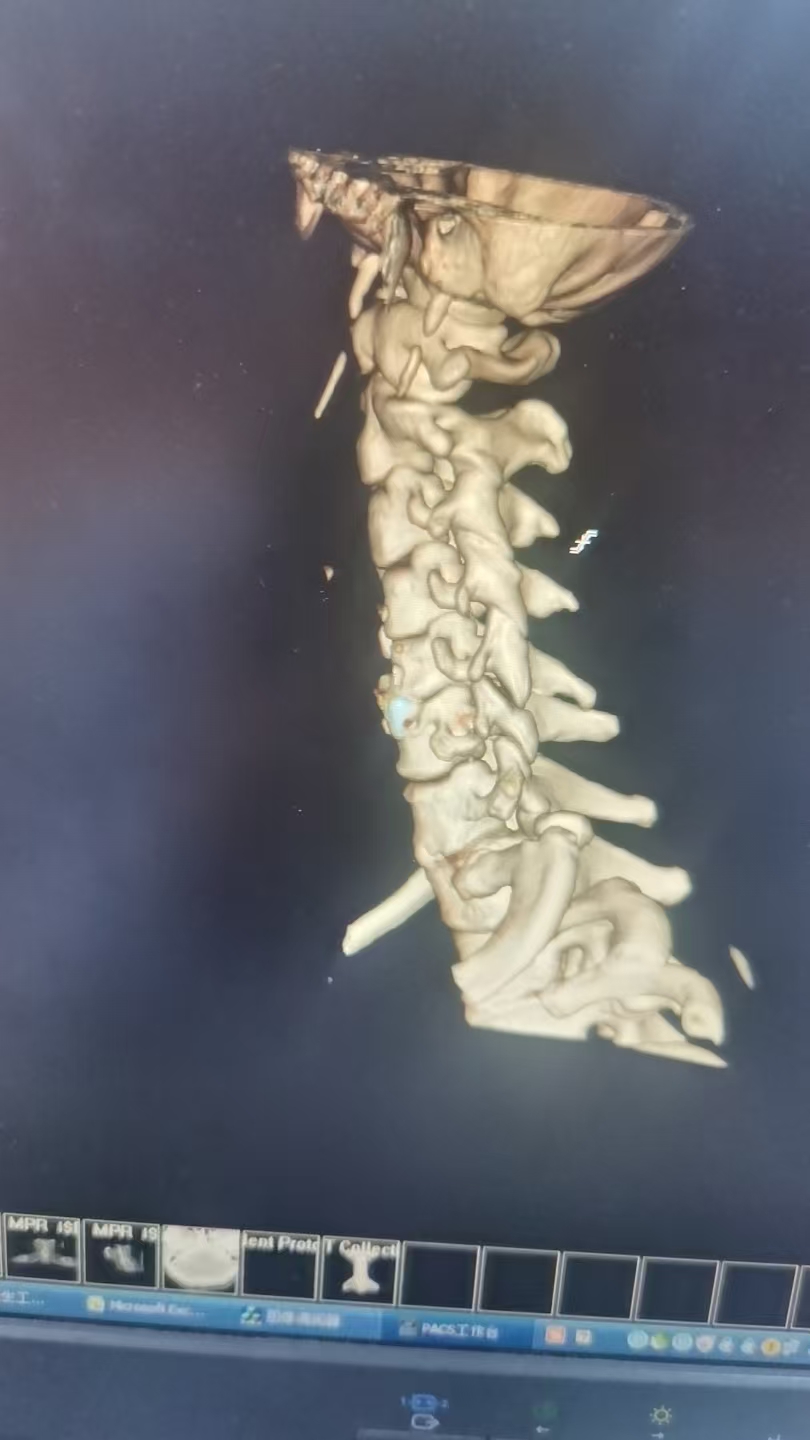

(术后图)

患者术后1小时意识清醒,生命体征稳定。术后神经功能较前有所改善,特别是右侧肢体肌力已达4级,为早期开展精细活动和力量训练创造了良好条件。